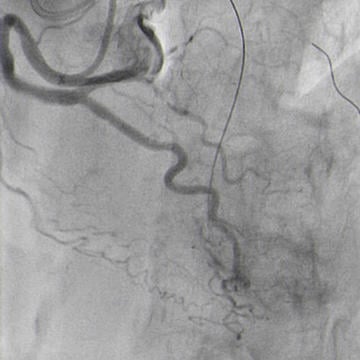

Double radial access with guiding catheter 6F JR 4.0 and sheatless 7.5F PB 3.5. Controlateral injection to check antegrade wire position via collaterals (Figure 4.1).

Antegrade guide wire position (Figure 4.1)